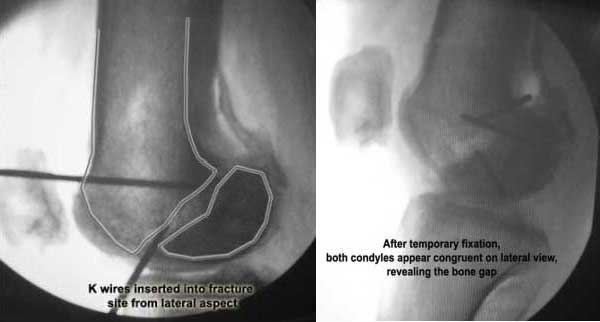

Applied a distractor between femoral shaft and tibia, to create a space on the lateral aspect.

This brought the lateral condylar fragment into a position that seemed to be reasonably well aligned, but showed up a bone gap.

This was fixed temporarily, bone grafted with tricortical struts, and fixed by two cancellous screws. The fragment was not large enough to afford any fixation to a plate or such implant, and the screws held it compressed well to the rest of the distal femur.

Pictures attached.